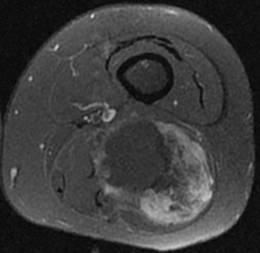

Synovialosarcome. Noter l’aspect hétérogène en T1, T2 et après injection de gadolinium